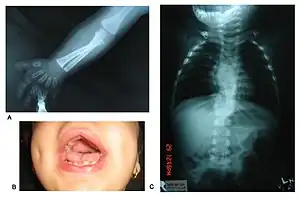

Note characteristic fetal face, hypogenitalism and brachydactyly of hands and feet.

X-ray upper limbs and hands showing mesomelic shortening and brachydactyly (A), gingival hyperplasia (B) and X-ray vertebrae showing hemivertebrae and vertebral fusion.

Patients suffer from dwarfism, short lower arms, small feet, and small hands. Fingers and toes may also be abnormally short and laterally or medially bent. The thumb may be displaced and some patients, notably in Turkey, experience ectrodactyly.[1] All patients often suffer from vertebral segmentation abnormalities. Those with the dominant variant have, at most, a single butterfly vertebra.[2] Those with the recessive form, however, may suffer from hemivertebrae, vertebral fusion, and rib anomalies. Some cases resemble Jarcho-Levin syndrome or spondylocostal dysostosis.[1]